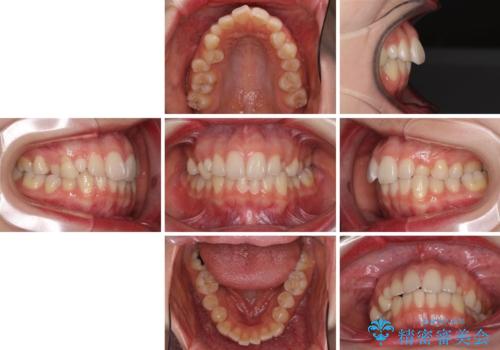

狭い上顎骨を拡大 急速拡大装置を併用したインビザライン矯正

- 前歯のクロスバイトや残存している乳歯を気にして来院された患者様です。

上顎骨の幅が下顎骨よりも小さいので、拡大装置により骨幅を広げて上下関係を改善し、その後インビザラインにて歯並びを整えることとしました。

上下の骨幅を改善したことで、スムーズに歯列矯正を行うことができました。

通院ペースが守れず治療期間が長くかかってしまいました。